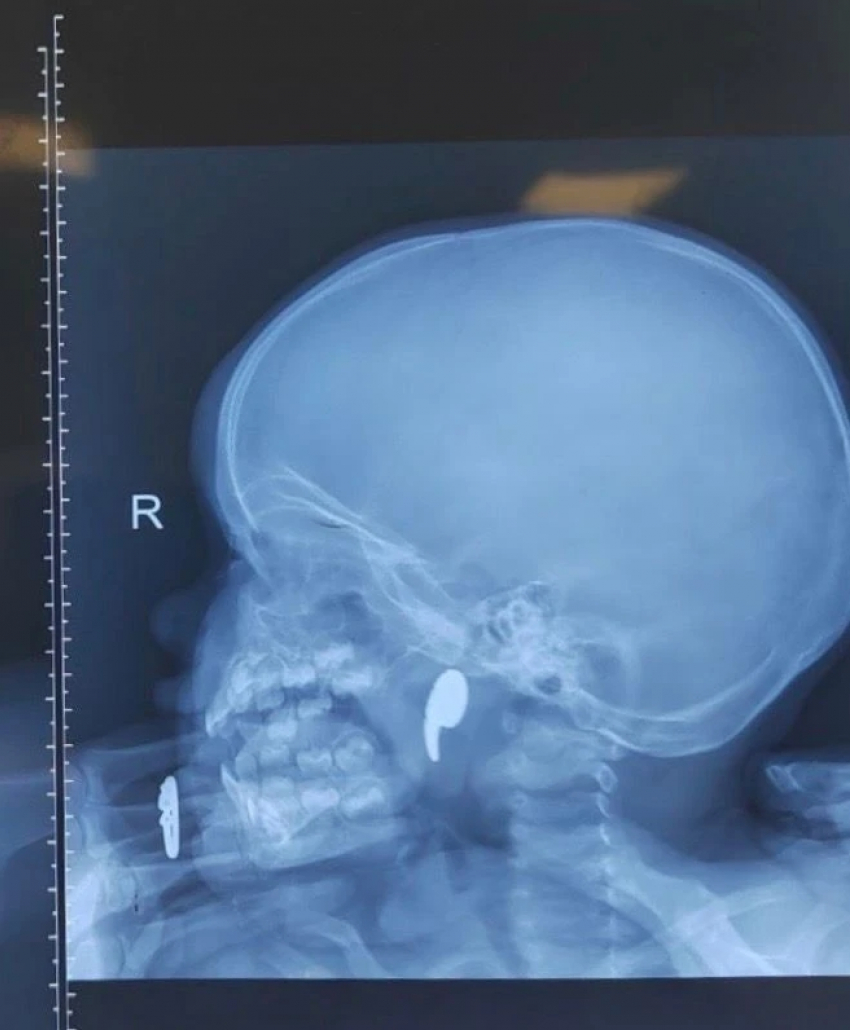

Девочка 1,5 лет попала в больницу №1 c болью в горле. Она не могла есть, активно текла слюна.

Врачи заподозрили в носу инородное тело. Мама рассказала, что ребенок играл с магнитом в форме запятой, начал давится. Мама пыталась вытащить его пальцем, но сместила его в носоглотку.

– Стоит отметить, что инородные тела, обнаруженные в носу, нередко встречаются в детской оториноларингологической практике. Однако нахождение магнита в носоглотке могло привести к удушью при попадании в гортань и трахею, что представило бы угрозу жизни ребёнка, – комментирует министерство здравоохранения.